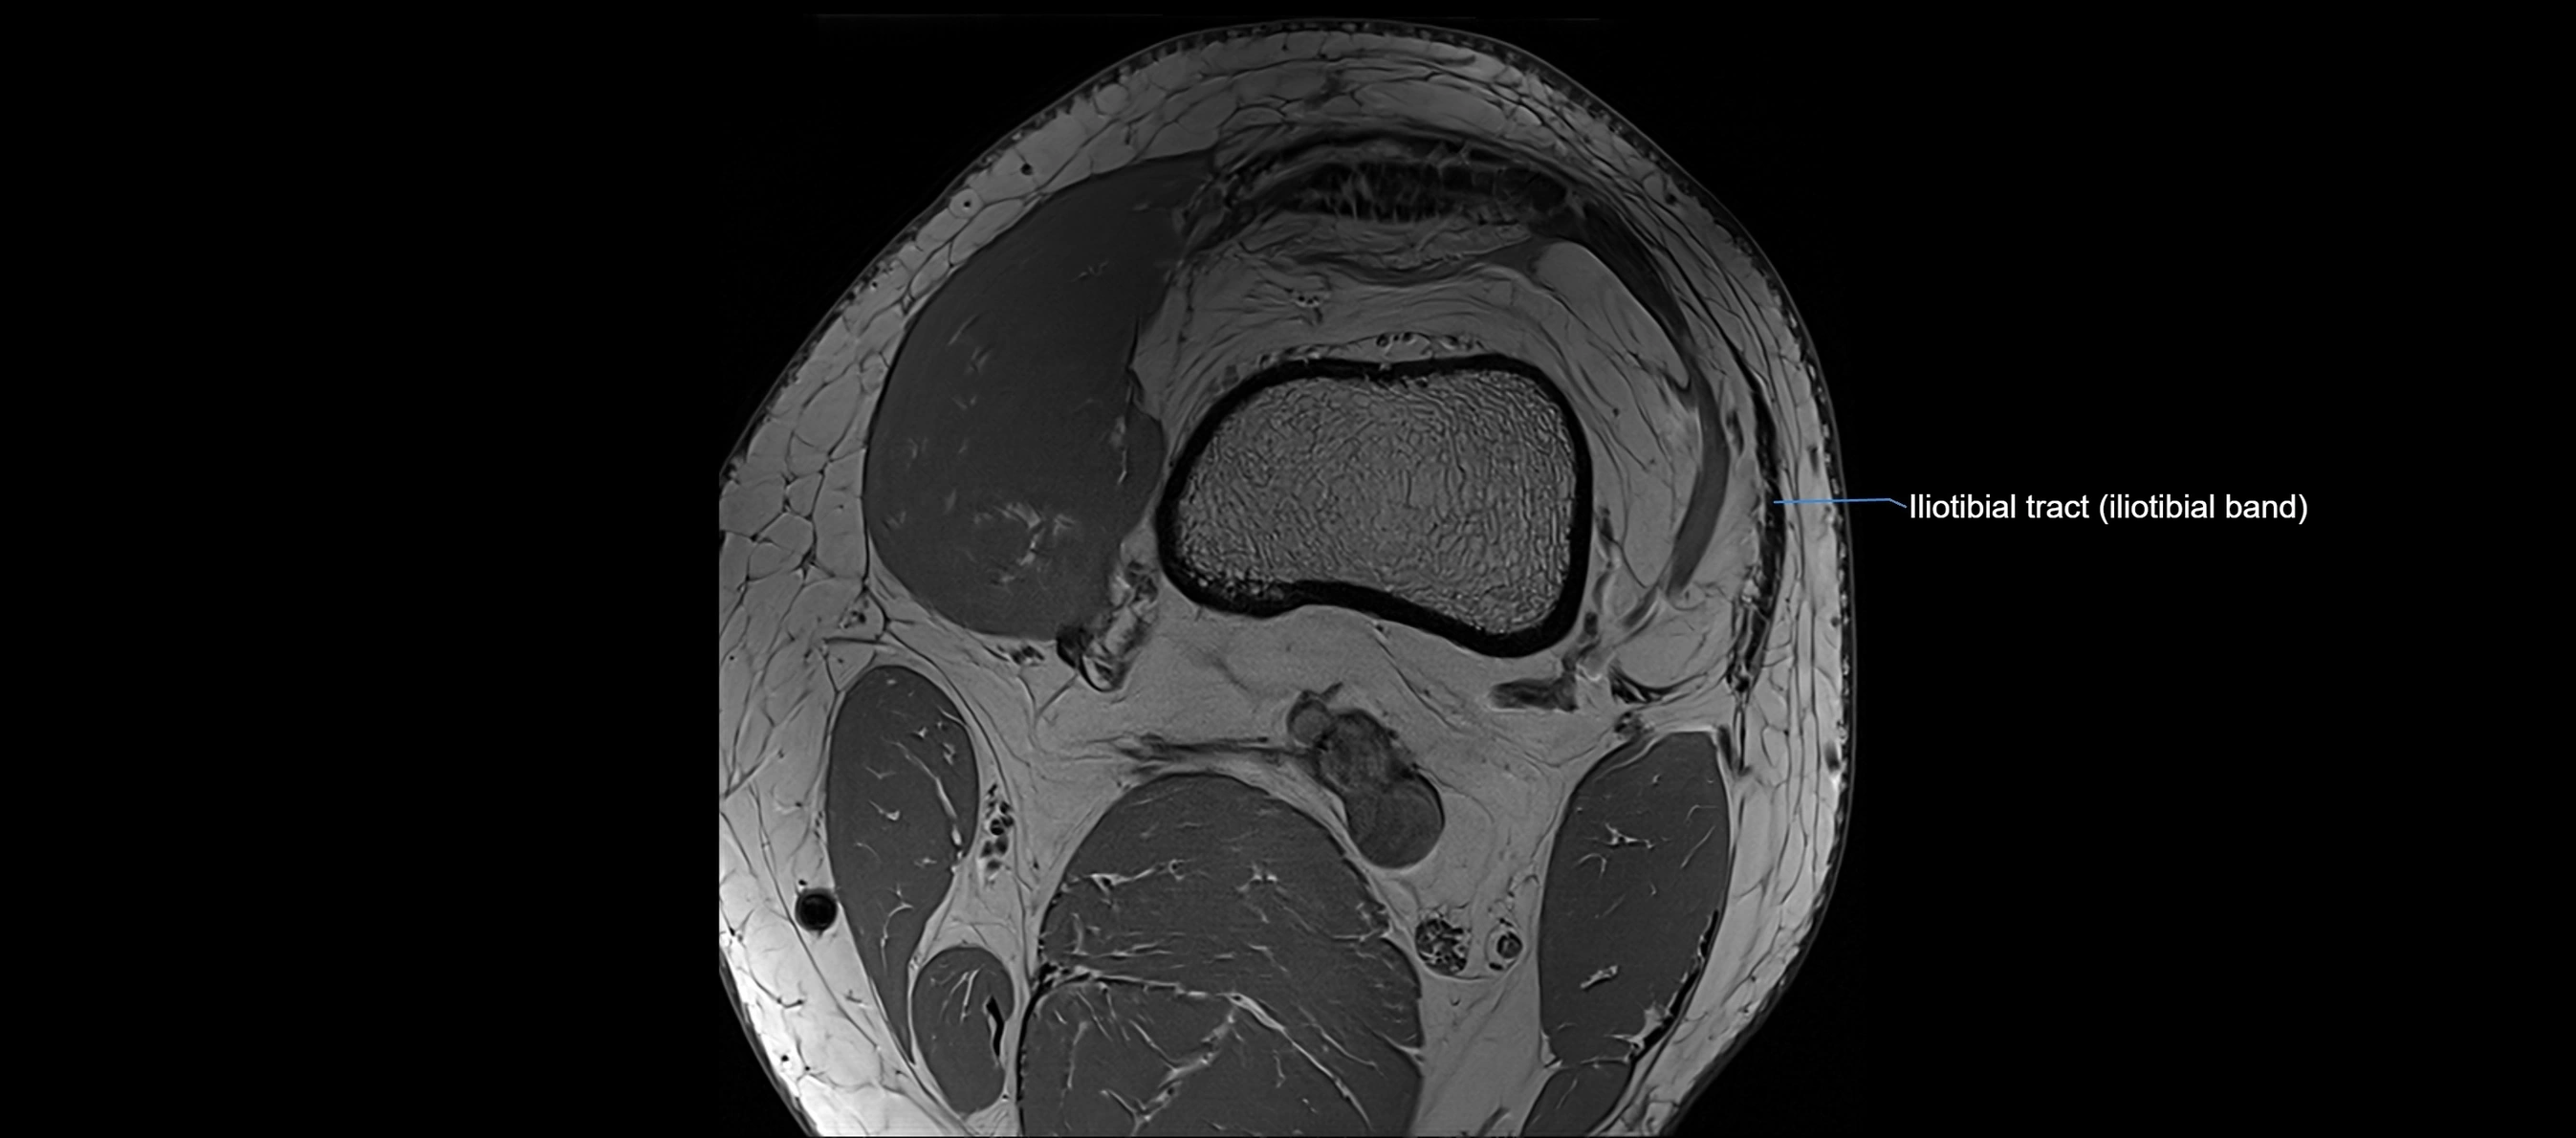

MRI Appearance

T1-weighted images:

• Normal ACL appears as a low-signal band-like structure crossing the intercondylar notch

• Surrounded by intermediate signal synovial fluid and fat planes

T2-weighted images:

• Normal ACL remains low signal

• Partial or complete tears appear as discontinuity, increased signal, or fiber laxity

STIR (Short Tau Inversion Recovery):

• Normal ACL shows dark low signal

• Acute injury shows bright hyperintensity due to edema and hemorrhage

Proton Density Fat-Saturated (PD FS):

• Normal ACL: dark, low-signal band

• Tears: bright intraligamentous hyperintensity, discontinuity, or abnormal course

MRI images

image